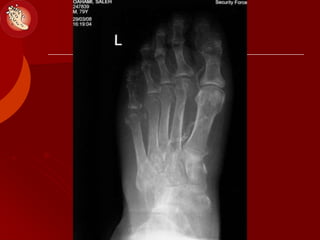

Patterns of Bone &Joint Destruction

(Ulcers & Charcot)

 Forefoot: MTP, IP

 Lisfranc:

 Chopart: TN-, CC- joint

 Ankle joint

 Calcaneus

Patterns of Bone&Joint Destruction (Ulcers & Charcot)  Forefoot: MTP, IP  Lisfranc:  Chopart: TN-, CC- joint  Ankle joint  Calcaneus MIS